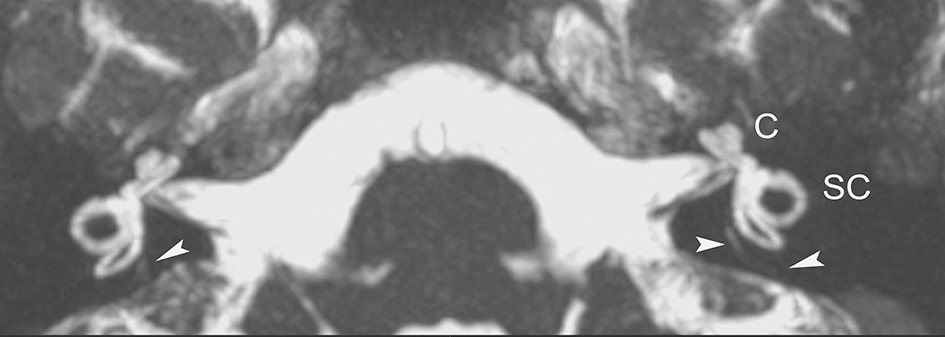

Axial non gadolinium-enhanced 3D-CISS image (with MIP technique) delineates normal anatomy of the inner auditory canal and the membranous labyrinthine structures on both sides, in a 16-year-old patient with vertigo and left ear tinnitus. At this image level, portions of the VA (arrowheads) can be seen. C, coclea; SC, semicircular canals.

In our clinical and imaging practices, we recommend that MR imaging be considered in patients with otovestibular symptoms, suggestive of MD. To this end, we have advocated a simple MR imaging protocol of the inner ear that would employ the 3D-constructive interference in steady state (3D-CISS) sequence (or equivalent fast gradient-echo pulse sequence). The CISS sequence is readily available in most high-strength (1.5 T or above) MR units and allows for fast acquisition of submillimeter high resolution images and multiplanar reconstructions that facilitate delineation of fine structures in the inner ear, and the JB. Because of a direct cisternographic effect that enables direct depiction of the vestibulocochlear lymph space, visualization of the minute anatomic structures in the membranous labyrinth (including the VA) and the acoustic nerves is feasible, sparing the administration of gadolinium material (9). Additional, post-processing maximum intensity projection (MIP) images with a slab thickness 4–5 mm generated form the original MR data may further increase conspicuity of the fine inner ear structures (Figure 1).